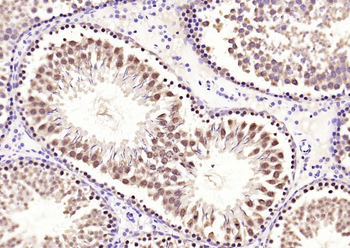

50 μl, 100 μlPhospho-Smad3 (Thr179) Rabbit Polyclonal Antibody [orb313112]

FC, ICC, IF, IHC-Fr, IHC-P

Bovine, Canine, Equine, Porcine, Sheep

Human, Mouse, Rat

Rabbit

Polyclonal

Unconjugated

100 μl, 200 μl, 50 μlSMAD7 Rabbit Polyclonal Antibody [orb500819]